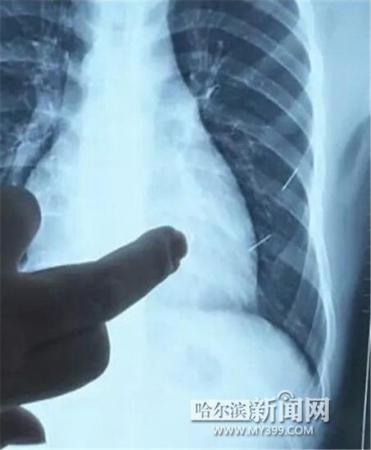

醫(yī)生指出X光片上的針狀物

昨日上午,記者在哈醫(yī)大二院第八住院部心外三病房找到了躺在病床上痛苦不堪的董立仁,家屬正在他身旁不斷安慰著他。見記者前來,董立仁母親李百燕拿出一張X光片,上面可以清晰地看到胸腔內(nèi)一共有4根針狀物,其中一根在心臟部位,兩根在胸腔壁上,還有一根在腹腔壁上。

心外三病房董立仁的主治醫(yī)生告訴記者,董立仁送到醫(yī)院時病情很危險,隨時可能危及生命?!巴ㄟ^檢查發(fā)現(xiàn),他心臟內(nèi)有一個金屬異物,正好在心臟上。心臟每次跳動都與其產(chǎn)生摩擦,導致出血,心包積液懷疑是血液。如果大量出血會凝結成血塊,血塊包裹住心臟就會影響心臟跳動,隨時都有停跳的危險。心臟上的異物是致命傷,其余胸腔壁和腹腔壁的異物傷害不大。”

昨天16時30分左右取針手術開始。因鋼針隨時會危及患者生命,此次手術定義為大型手術。開胸后,醫(yī)生打開董立仁心包,發(fā)現(xiàn)一枚鋼針已深深扎入心臟,僅露出1厘米長度在外。拔出鋼針后,醫(yī)生發(fā)現(xiàn),這枚針長達5厘米。受鋼針影響,心包出現(xiàn)大量積液,近800毫升。

隨后,在下胸壁位置,第二枚鋼針順利取出。在尋找另兩枚鋼針過程中,普外、胸外多名醫(yī)生也參與手術,為主刀醫(yī)生提供更為穩(wěn)妥的處理建議。根據(jù)X光片顯示位置,醫(yī)生未在患者體內(nèi)找到剩余兩枚鋼針。醫(yī)生懷疑,其中一枚鋼針可能深藏在肋骨骨膜位置,無法尋找,最后決定結束手術,做進一步觀察,研究下一次手術方案。